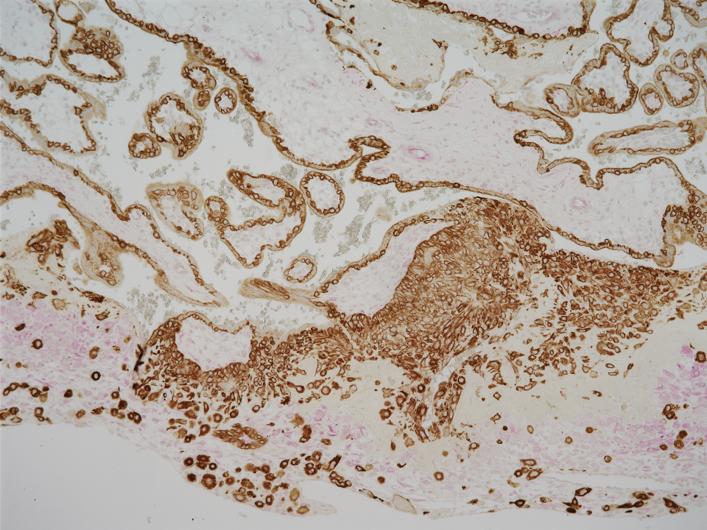

Trophoblast Cells

image: In preparation for pregnancy, fetal trophoblast cells (brown) from which the placenta arises invade maternal decidual cells (pink) in the uterus lining. view more

Credit: Image courtesy of Hana Totary-Jain of USF Health, originally published in Scientific Reports: doi.org/10.1038/s41598-020-59812-8